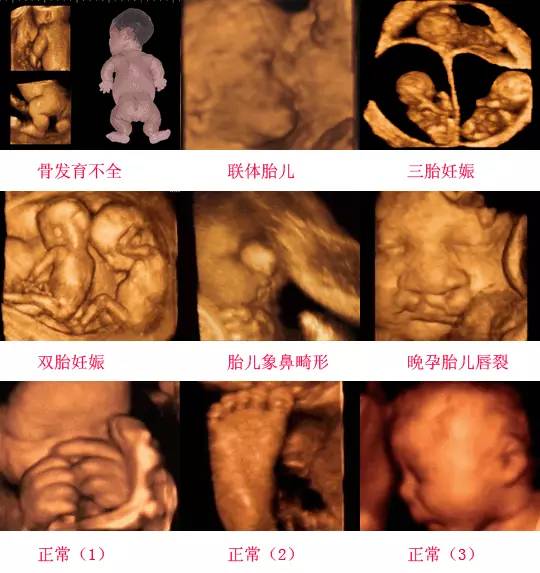

在四維彩超下,胎兒蛋蛋呈現(xiàn)出特定的形態(tài)和外觀,通常情況下,胎兒蛋蛋呈現(xiàn)出圓形或橢圓形,表面光滑,內(nèi)部回聲均勻,隨著胎兒的發(fā)育,蛋蛋會(huì)逐漸增大,并呈現(xiàn)出明顯的性別特征,醫(yī)生可以通過(guò)四維彩超技術(shù),對(duì)胎兒蛋蛋的大小、形態(tài)和位置進(jìn)行評(píng)估,以判斷胎兒生殖系統(tǒng)的健康狀況。

四維彩超技術(shù)在評(píng)估胎兒蛋蛋發(fā)育方面具有重要意義,通過(guò)四維彩超,醫(yī)生可以實(shí)時(shí)觀察胎兒蛋蛋的形態(tài)、位置和大小等特征,了解胎兒生殖系統(tǒng)的發(fā)育情況,四維彩超還可以幫助醫(yī)生發(fā)現(xiàn)可能的異常情況,如睪丸未降、睪丸囊腫等,為及時(shí)采取治療措施提供依據(jù)。